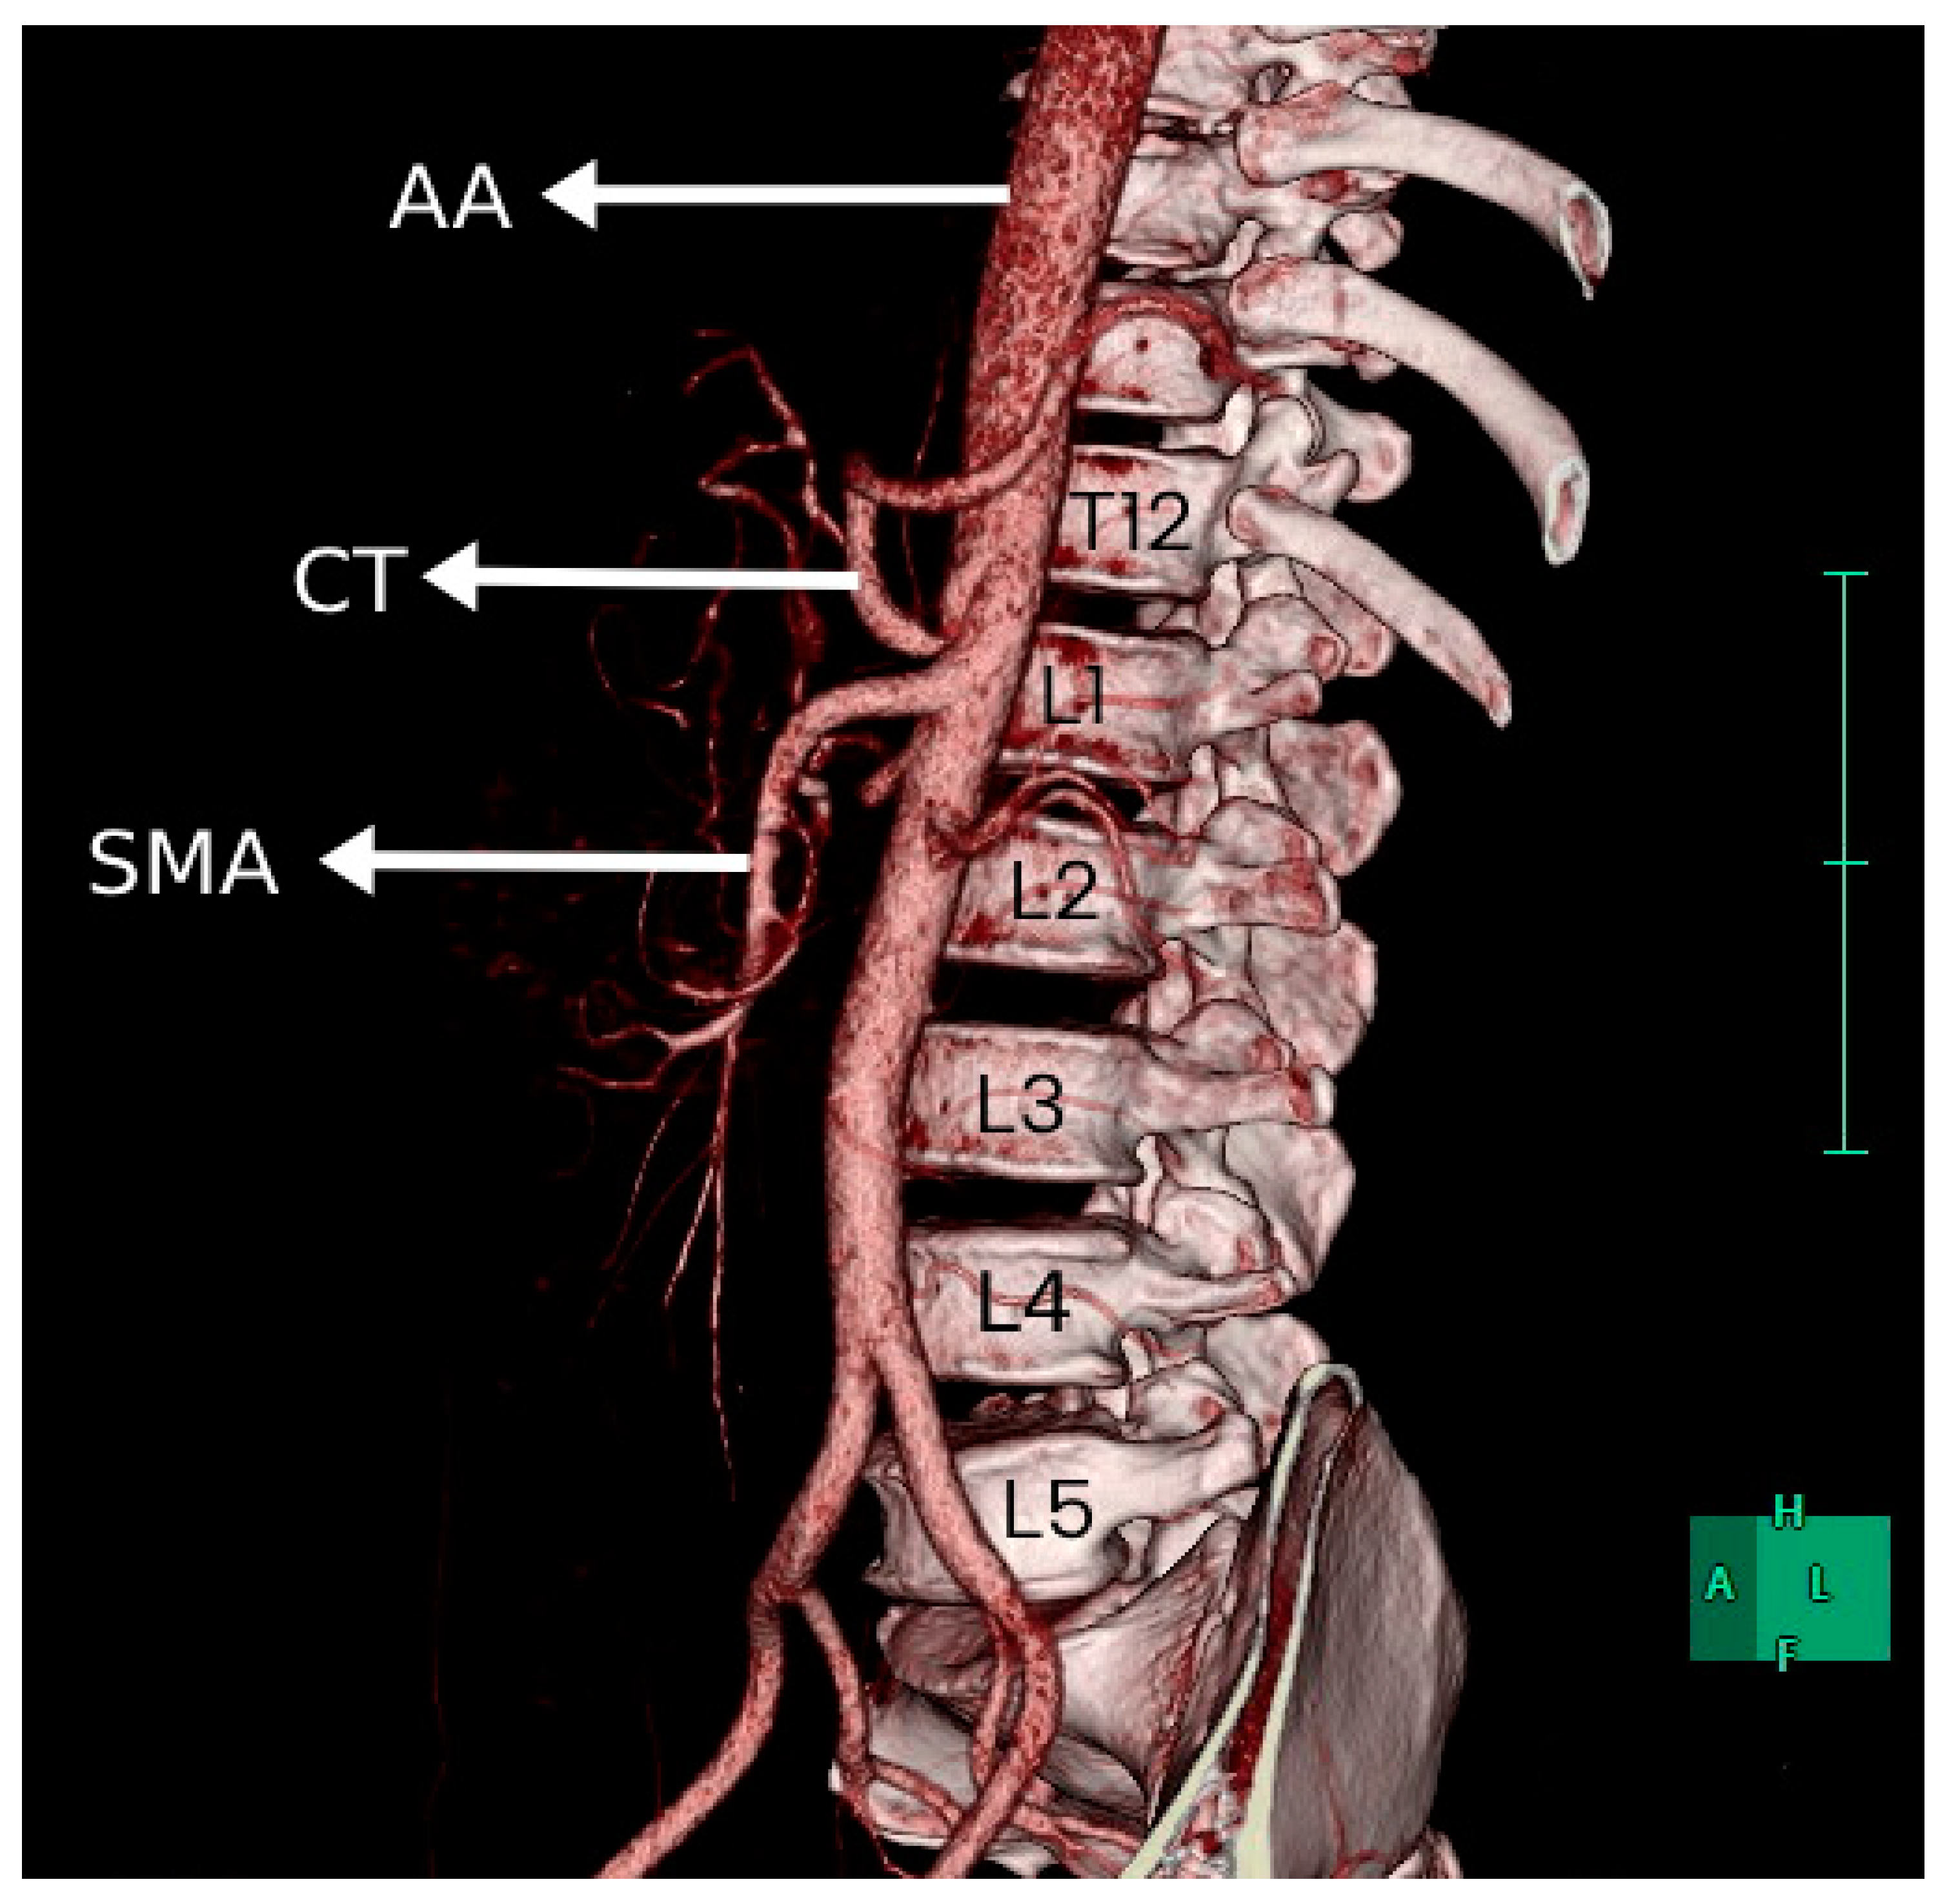

In 85 patients (73.3%), the CT originated at the level of the T12 vertebra. In 25 patients (21.6%), the CT took origin at the level of the L1 vertebra. Figure 3 shows a 3D image of the CT originating at the level of L1. In the other six patients (5.2%), the CT originated from the abdominal aorta at the level of T11. Figure 4 shows the CT originating at the level of T11. The levels at which CT originated in males and females are shown in Table 1.

Figure 3. Three-dimensional reconstruction showing the CT originating at the level of L1. Superior mesenteric artery (SMA), celiac trunk (CT), and abdominal aorta (AA).